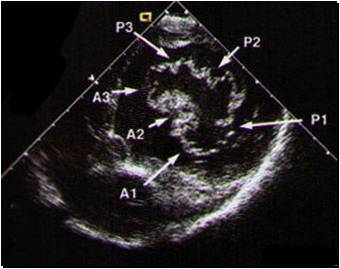

This is looking down to mitral valve

I think this might be the most important picture for TEE